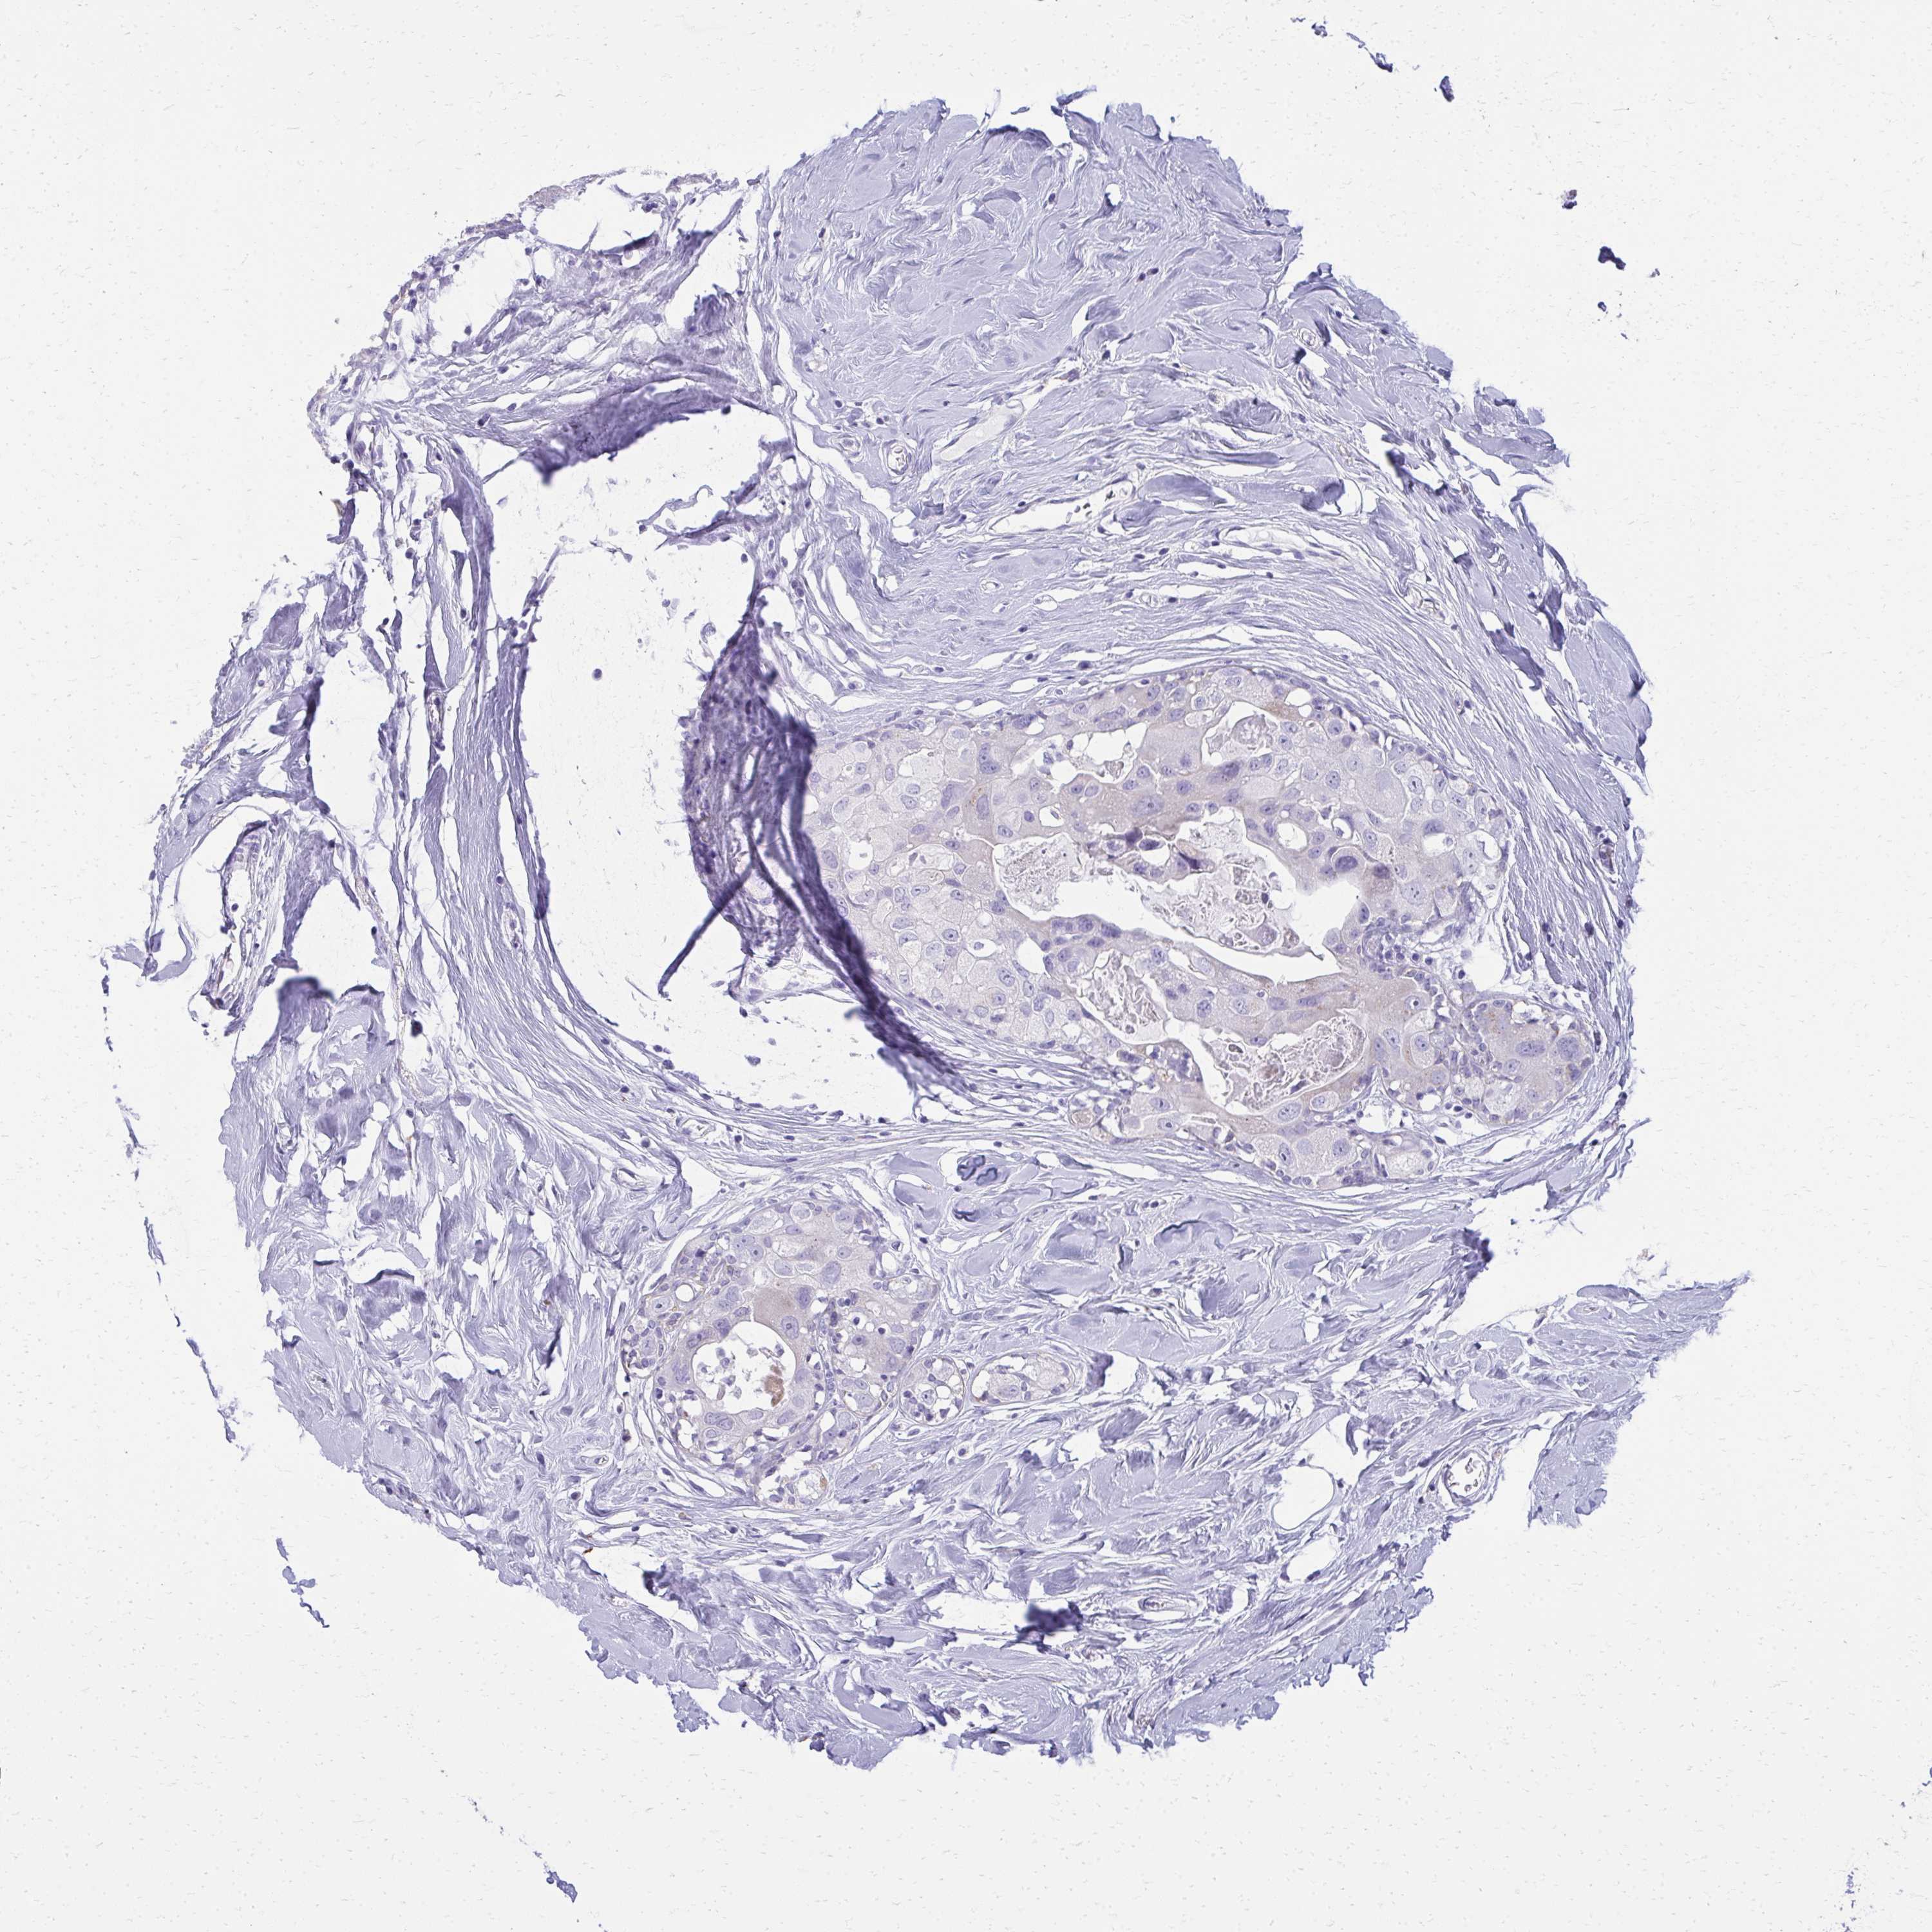

Breast cancer

Human cancer